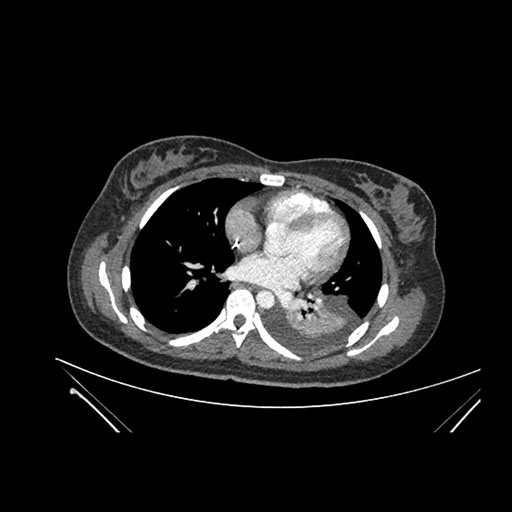

Imaging Analysis

Look through the patient's CT scan to identify any areas of concern for the necessary procedure.

Axial Arterial

Based on initial findings, which issue(s) would you be most concerned about?